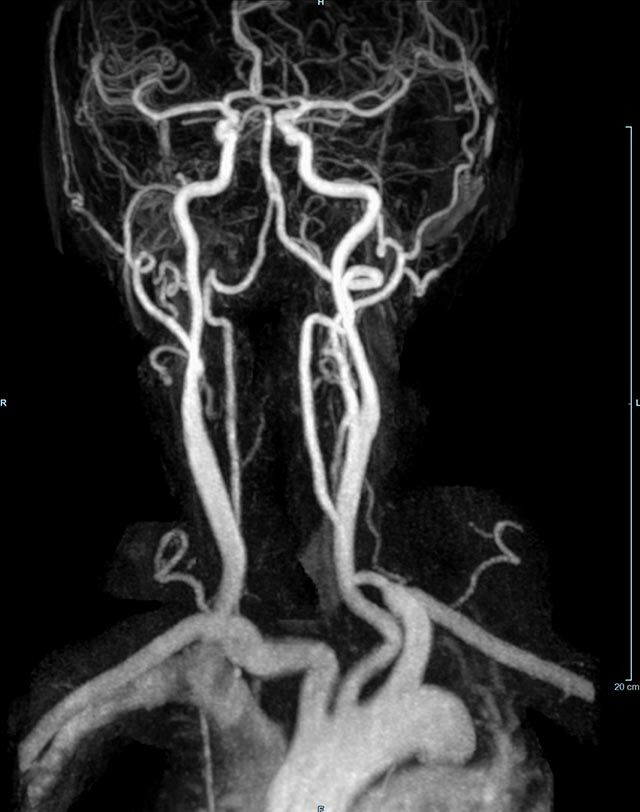

Kopf/Hals

• akute Schlaganfalldiagnostik und chronische Durchblutungsstörungen

• intrakranielle Gefäße (Abklärung Verschluss, Stenose, Aneurysma)

• Halsgefäße zur Therapieplanung (z.B. Stent, Operation)

MR-Angiografie (MRA)

• MR-Angiografie ohne Kontrastmittel

• Time of Flight (TOF)-Angiographie

Je nach Fragestellung und Körperregion Gefäßdarstellung ohne Kontrastmittel bei Kontrastmittelunverträglichkeit oder terminaler Niereninsuffizienz möglich.

• MR-Angiographie mit Kontrastmittel

• Erfassung arterieller und venöser Gefäße/Bypässe aller Körperregionen mit 3D-Rekonstruktion